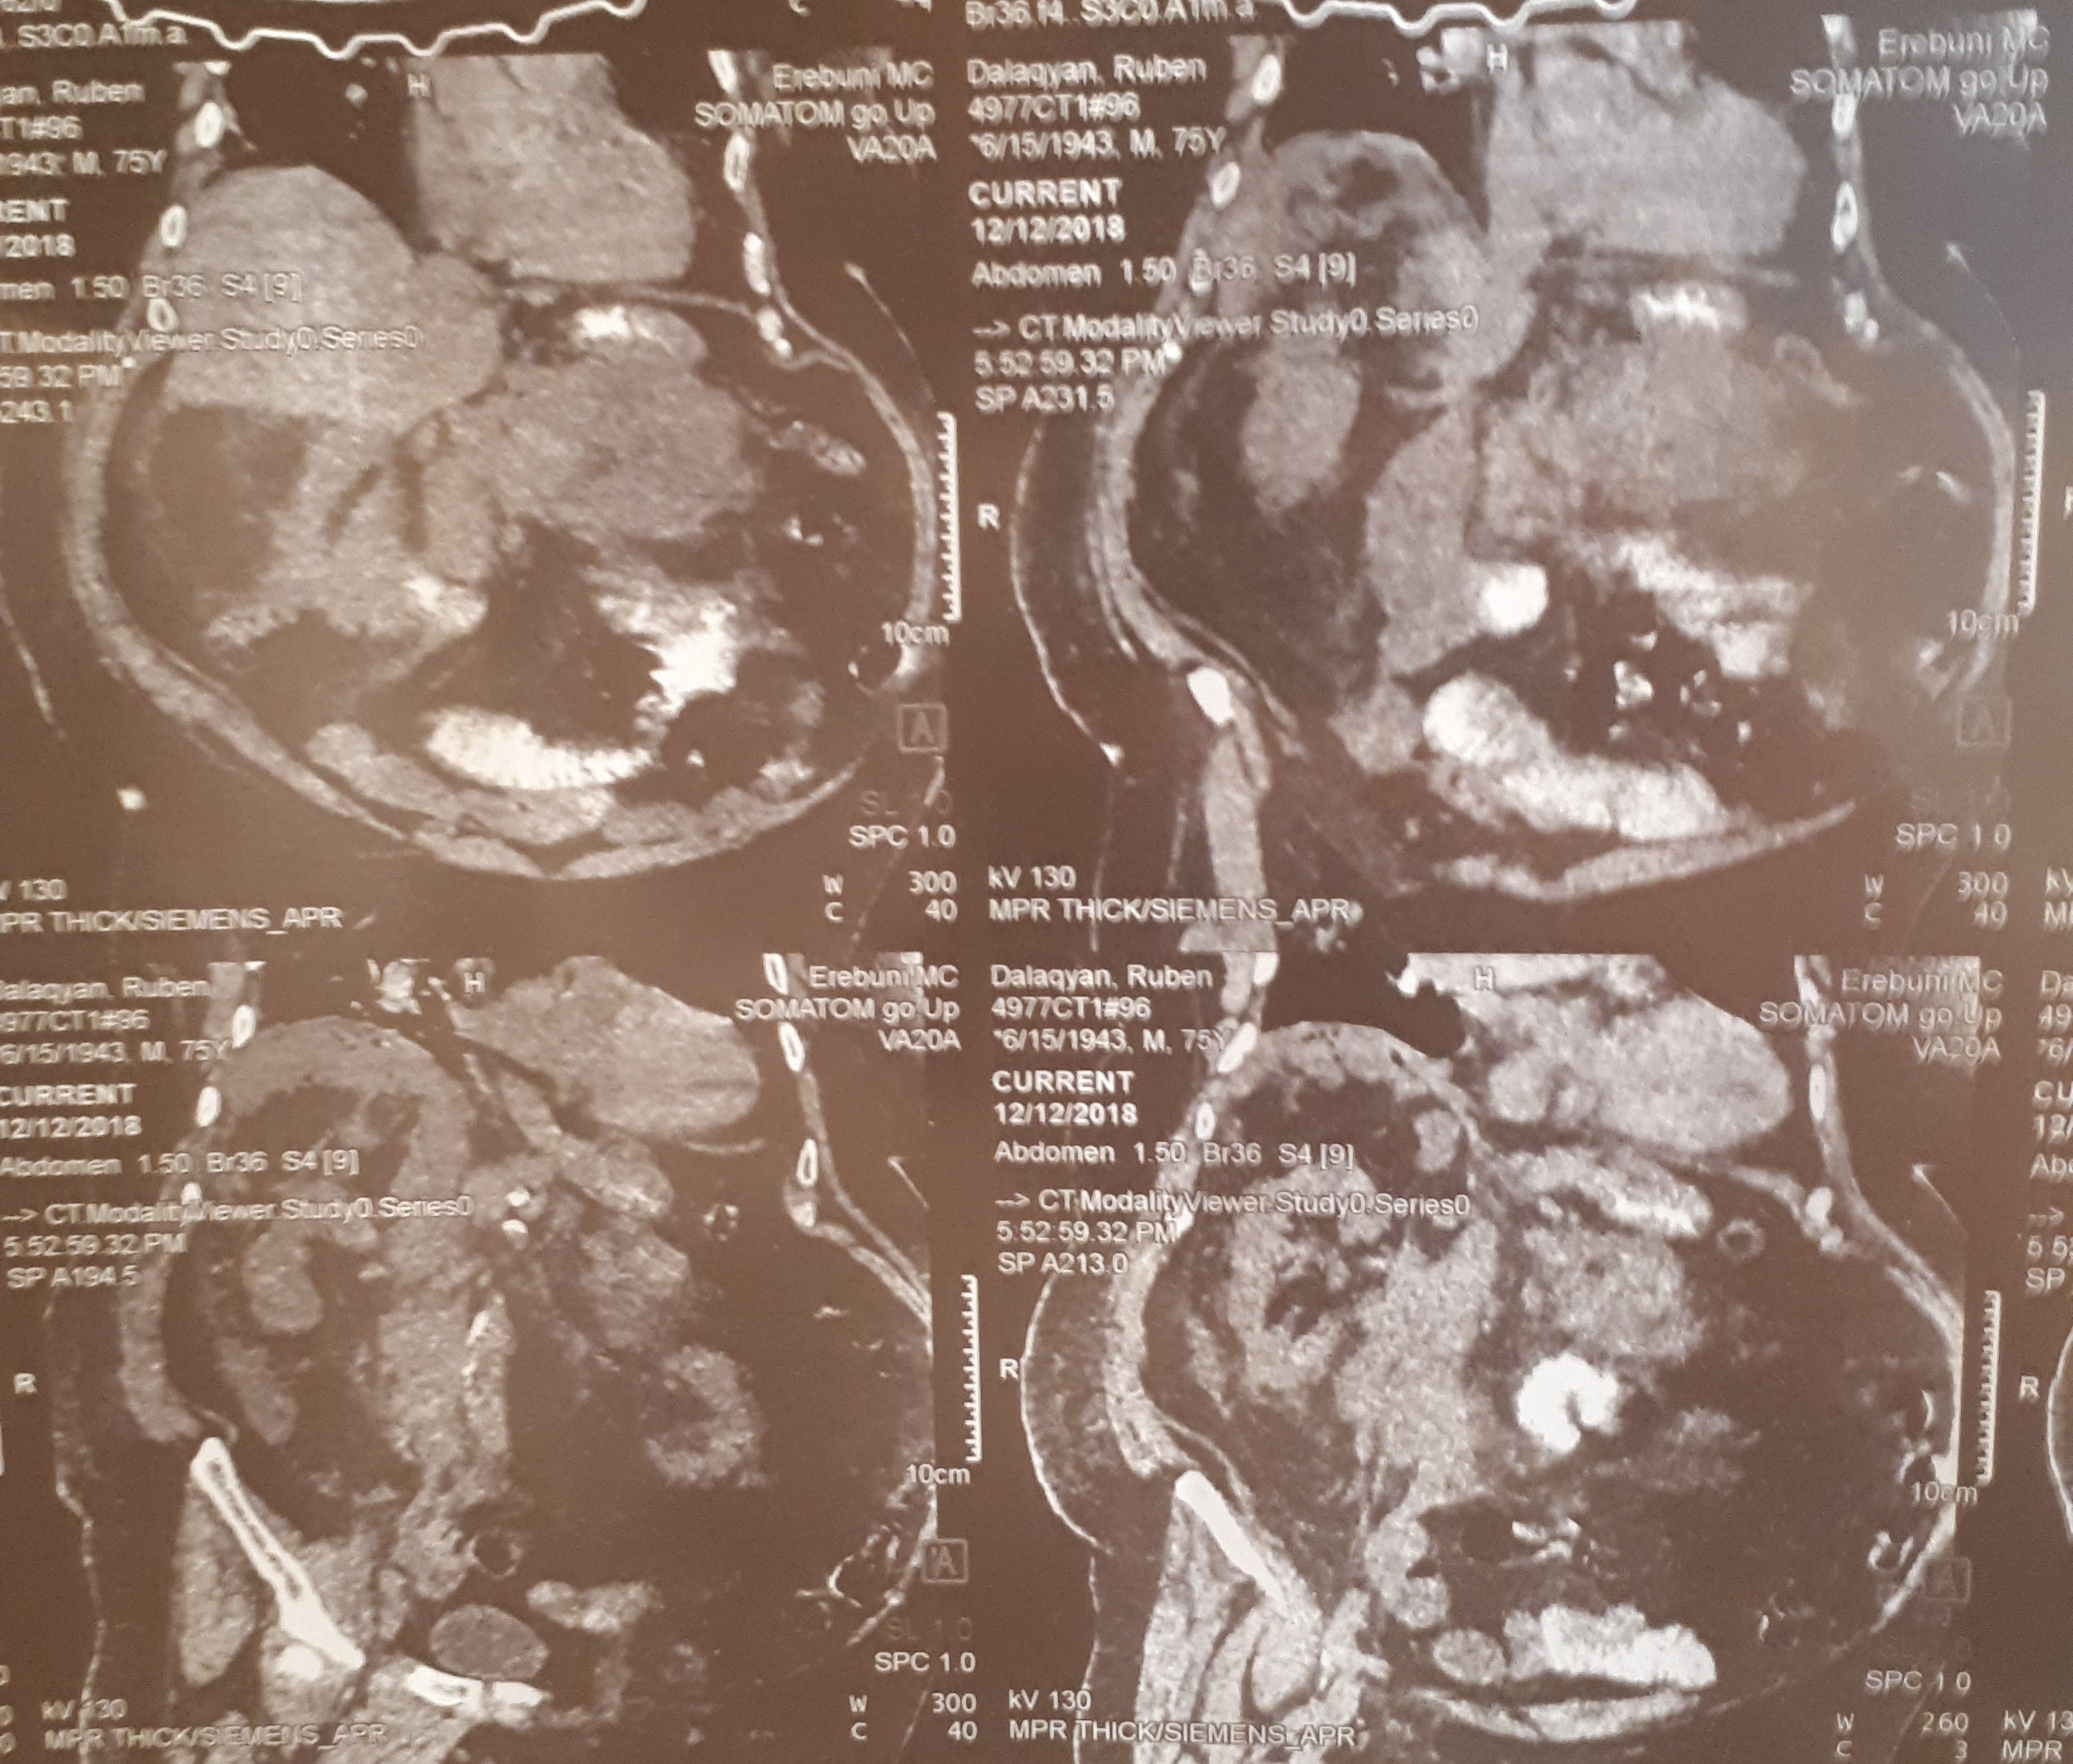

տղամարդը եւ հիպերտենզիա ԱՓՇ-ում…Այս խնդիրների դեպքում բաց վիրահատությունը ուղղակի հակացուցված է: Արա Վարդանյանը ընտրել է այլ ճանապարհ: Առաջին հերթին՝ տեղային անզգայացման պայմաններումուլտրաձայնայինհսկողությամբ իրականացվել է հետորովայնամզային տարածության թարախակույտի դրենավորում, հաջորդ օրը կատարվել է ճարպոնային ծոցի դրենավորում: Սահմանվել է դինամիկ հսկողություն եւ կոնսերվատիվ թերապիա: Ինֆուզիոն, հակաբակտերիալ, սիմպտոմատիկ թերապիան շարունակվել է վիրաբուժական բաժանմունքում: Սրանով, սակայն, բուժումը չի ավարտվել: Մի քանի օր անց դրենավորվել է նաեւ աջից ենթադիաֆրագմալ տարածությունում առկա թարախակույտը: Հիվանդը ստոցիոնարում բուժումը շարունակել է եւս մի քանի օր եւ դուրս գրվել հիվանդանոցից բավարար վիճակում, ճարպոնային ծոցի եւ հետորովայնամզային տարածության գործող դրենաժներով: Նա, իհարկե, կշարունակի մնալբժշկի հսկողության տակ, բայց վերադարձել է նախկին կենսակերպին, ցավային զգացողություններ չունի: